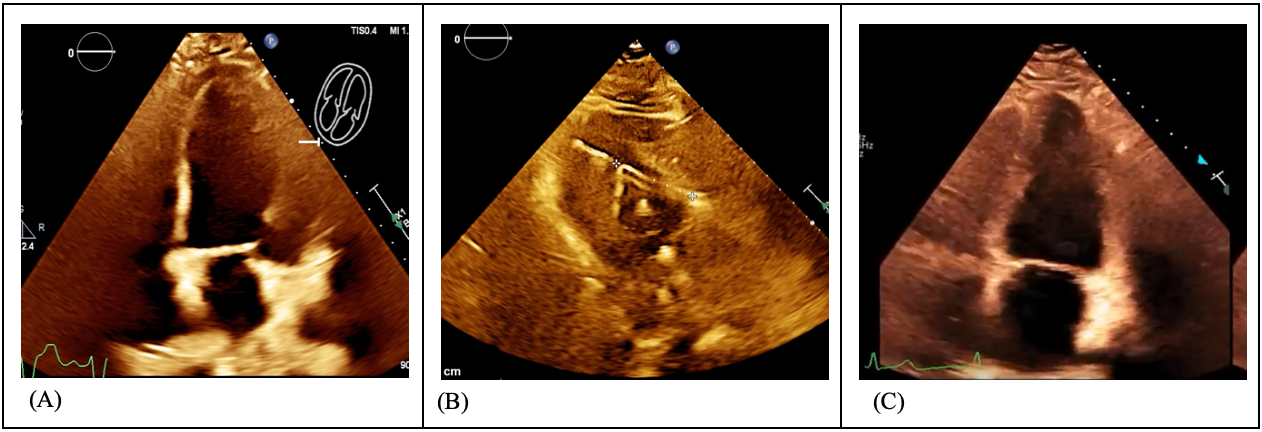

A 72-year-old male with chronic obstructive pulmonary disease, peripheral artery disease, heart failure with reduced ejection fraction (25–30%), diabetes, hypertension, and stage III chronic kidney disease presented with acute hypoxic respiratory failure. Initial labs showed severe acidosis. He experienced pulseless electrical activity arrest followed by asystole, requiring resuscitation and intubation. After return of spontaneous circulation, complete heart block developed, requiring transvenous pacemaker (TP) placement. The patient had multiple episodes of unstable VT, needing five defibrillations before catheterization and maximal pressor support (Figure 1). Right heart catheterization revealed cardiogenic shock; left heart catheterization showed severe three-vessel coronary artery disease, including critical left main stenosis. VT recurred during catheterization, requiring six more shocks despite amiodarone and lidocaine. Due to refractory VT and acidosis, an Impella CP was placed. VT resolved post-placement with no further cardioversion. Hemodynamic stability enabled continuous renal replacement therapy. Bypass surgery was deemed unsuitable. High-risk PCI with rotational atherectomy and drug-eluting stents was performed to the left main, anterior descending, and circumflex arteries. Intravascular ultrasound optimized stent deployment. TP was maintained during PCI. Following the procedure, Impella was weaned, and left ventricular function improved significantly (Figure 2). He was discharged in stable condition. This course is outlined in Figure 3.